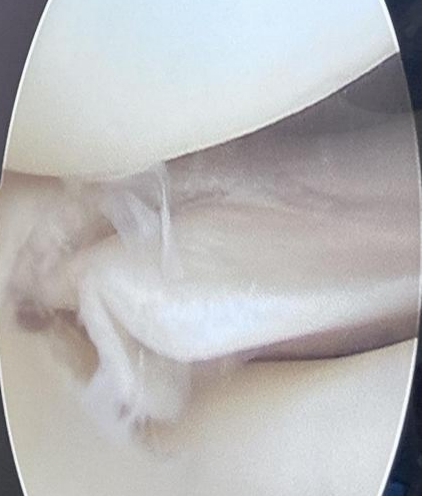

来自徽州区消防救援大队的徐XX,是一名优秀的消防战士,多年来他饱受膝关节伤病疼痛的折磨,反复发作,半年来膝关节疼痛明显家中伴行走活动受限,多次外院就诊无果,来我院骨伤科就诊,查右膝关节MRI提示右膝外侧半月板体部及前后角损伤(Ⅲ°)。因患者年龄较轻,对膝关节运动功能要求高,担心后遗症问题,医院及时组织专家团队和上海长征医院关节外科主任符培亮教授在线会诊,决定采取关节镜下半月板修复手术治疗,符教授亲临我院指导手术,经过详细的术前检查、评估、讨论,做好充分的术前准备前提下,于1月20日晚在会诊麻醉下,符培亮教授与我院骨科、手术室医护团队紧密配合,展现了高超的技术和精湛的医术,仅用20分钟就完成半月板缝合修复手术,并且术后进行广泛而深刻的学术讨论,为我科进一步攀登骨科高峰指引了方向。